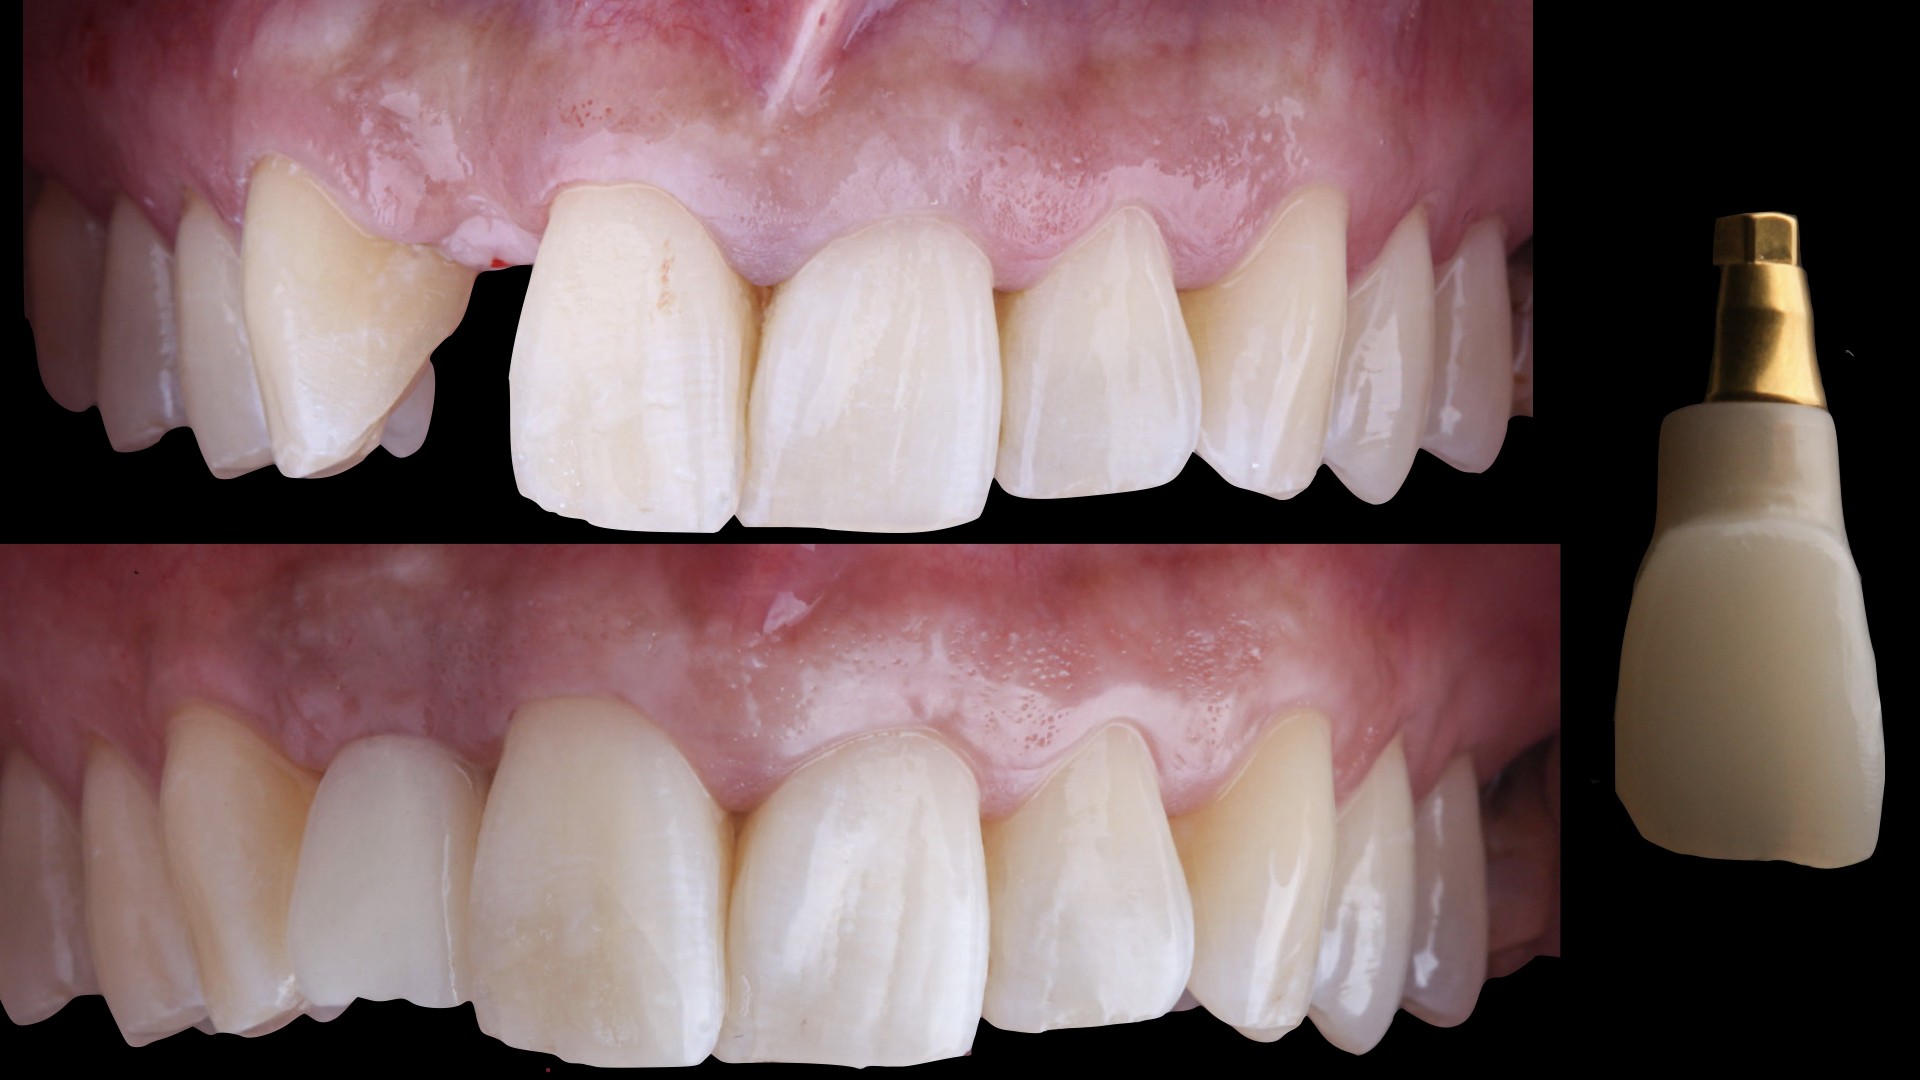

Métodos: Se llevó a cabo un caso clínico en una paciente de 40 años con fracaso de restauración fija dentosoportada en el incisivo central superior izquierdo, asociado a caries radicular subgingival con mal pronóstico restaurador. Tras la evaluación clínica y radiográfica, se indicó la exodoncia atraumática del diente afectado. Inmediatamente después, se realizó la colocación de un implante postextracción. El defecto periimplantario (gap) fue rellenado con un xenoinjerto óseo bovino. De forma simultánea, se llevó a cabo un injerto de tejido conectivo con el objetivo de optimizar el volumen y la estabilidad de los tejidos blandos periimplantarios. Se procedió a la colocación de una restauración provisional inmediata atornillada, diseñada para preservar el perfil de emergencia y guiar la cicatrización de los tejidos periimplantarios. Tras un periodo de cicatrización de cuatro meses, se colocó la restauración definitiva atornillada.

Resultados: El seguimiento clínico y radiológico evidenció una correcta osteointegración, estabilidad de los tejidos periimplantarios y un resultado estético satisfactorio, mantenido a los cuatro años.